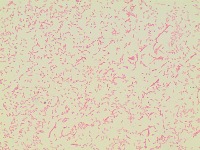

bacterial-image-classification Computer Vision Project

bacteriaclassification

Classes (78)

A description for this project has not been published yet.